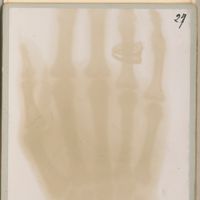

0053 - Page 29 - 20 mars 1896. - Balle masquée depuis deux ans. - 45 minutes de pose0053 - Page 29 - 20 mars 1896. - Balle masquée depuis deux ans. - 45 minutes de pose